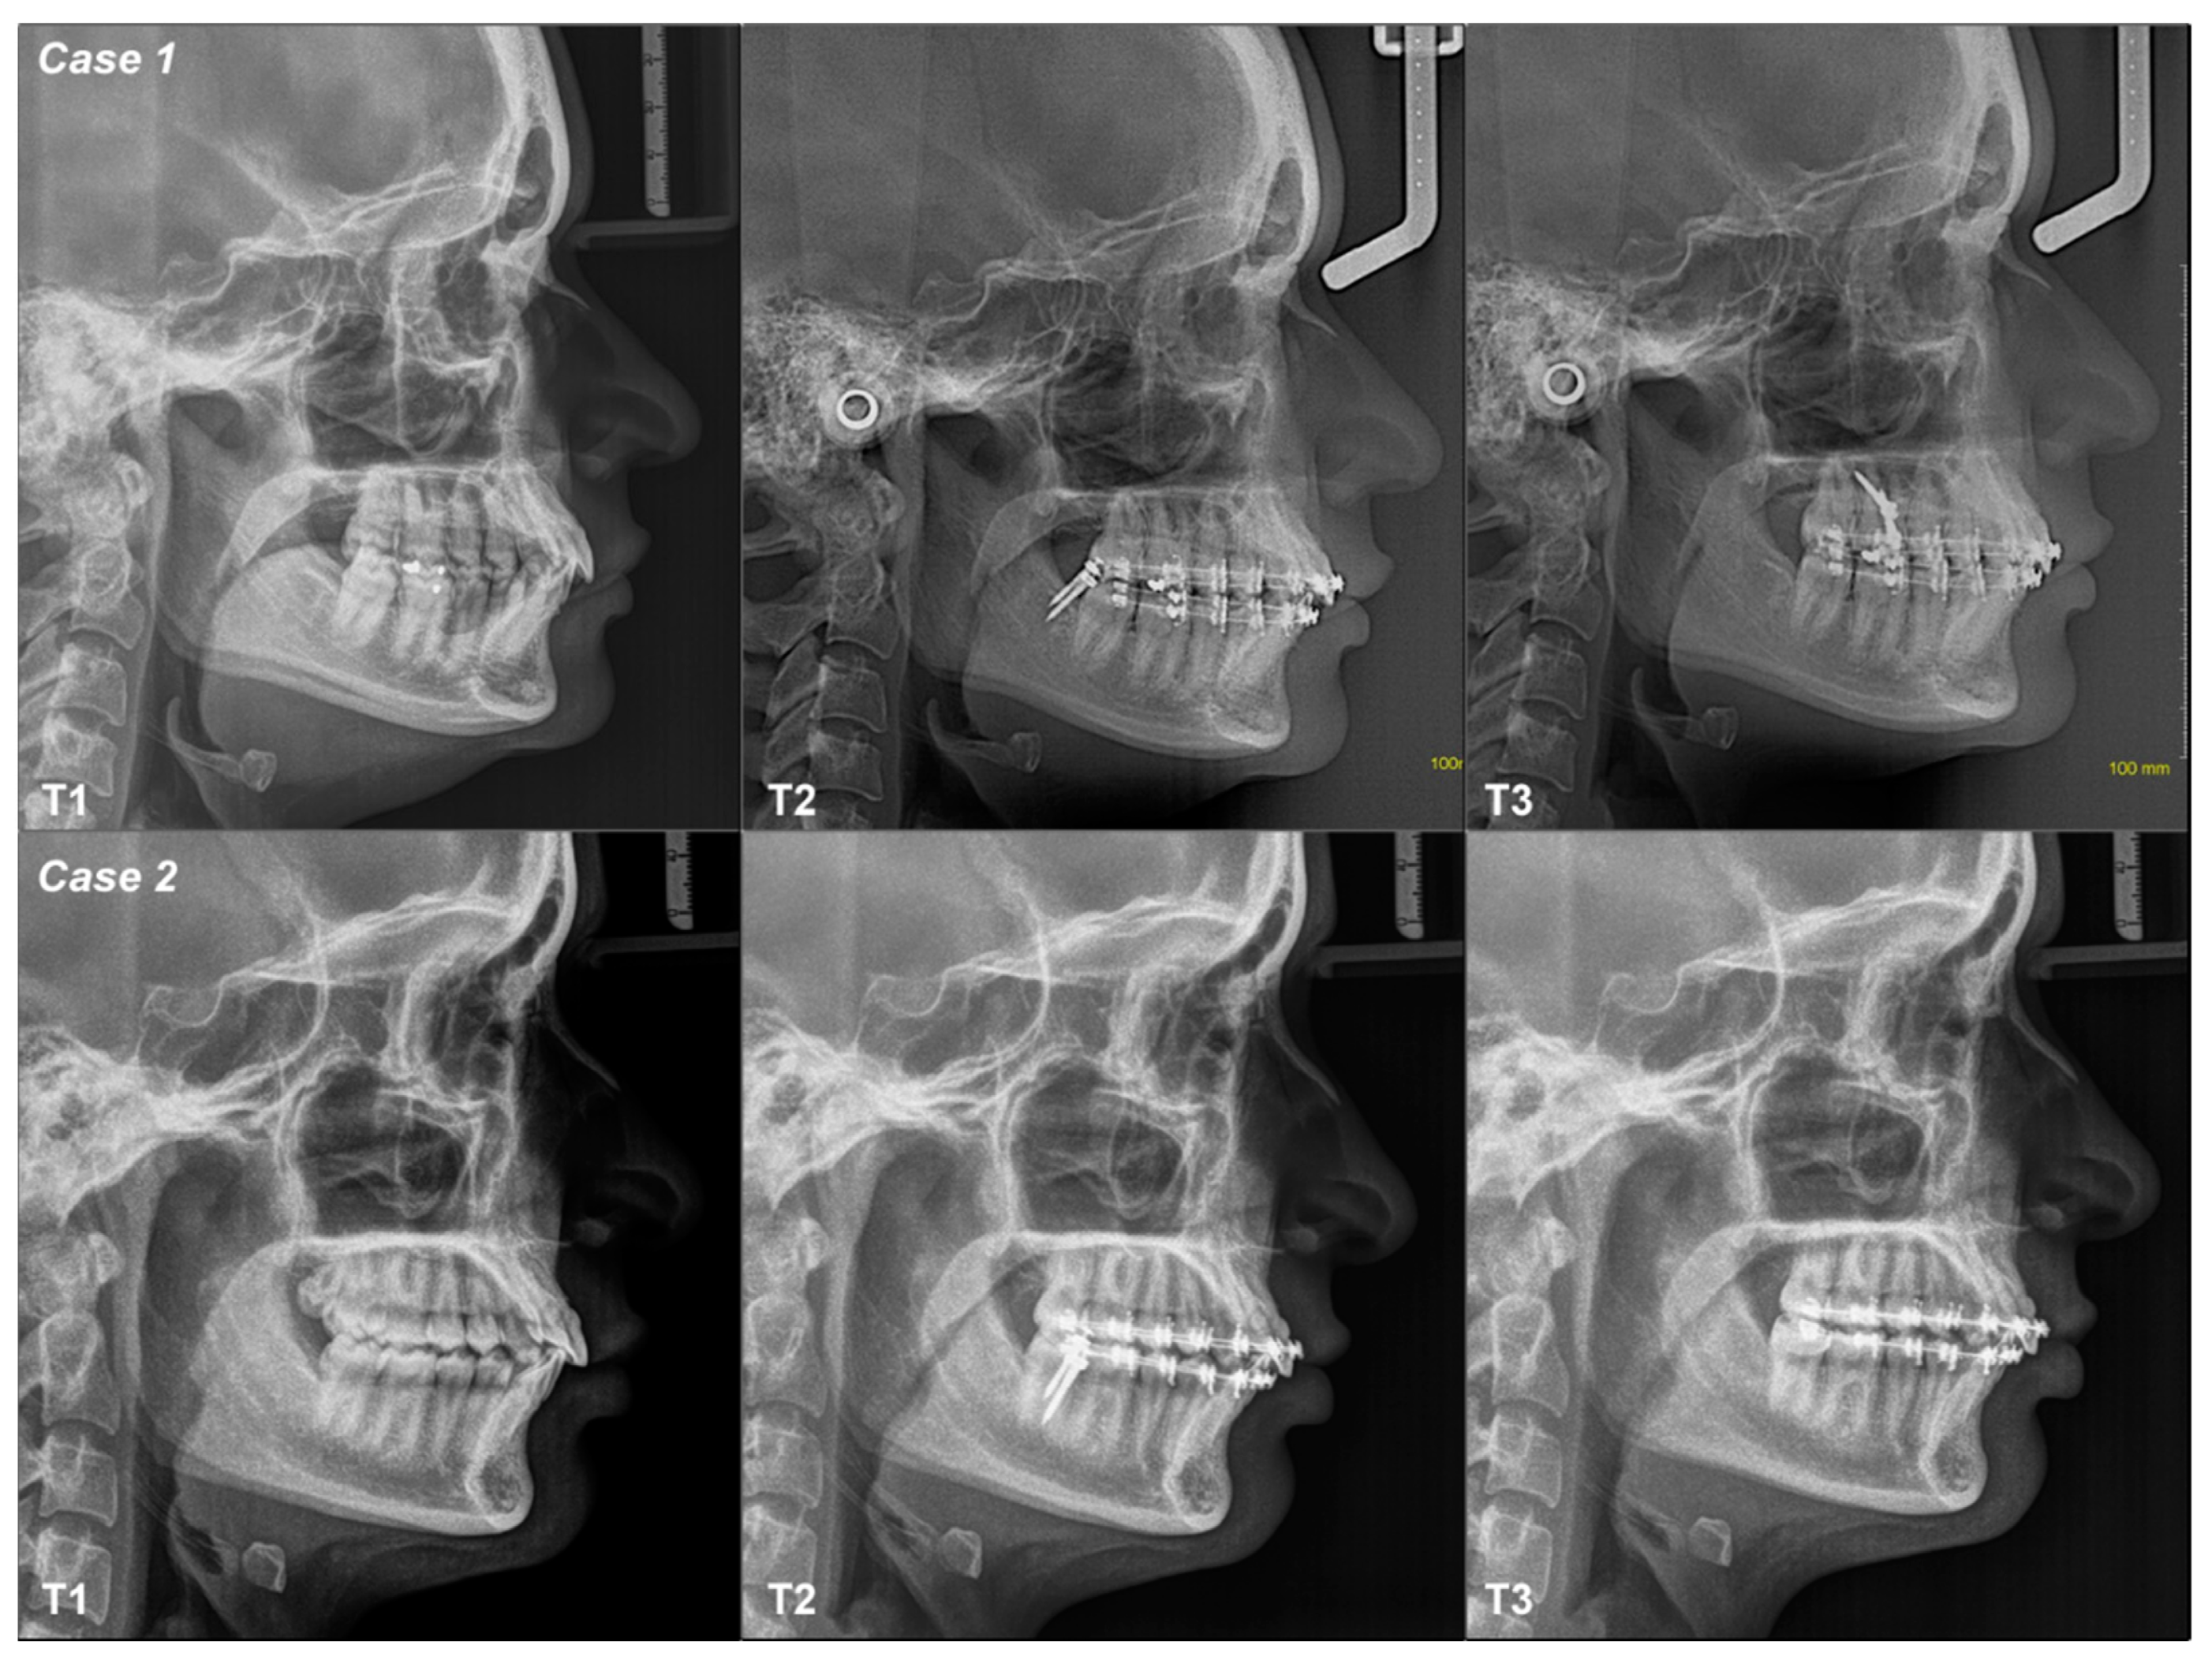

3.2.1. Case 1

3.2.2. Case 2

| 1 | Class I Neutral Angle | Mandible | T1–T2 | Flattened | Tipped | Flattened | Decreased | Increased | Decreased | Not changed | Not changed |

| T2–T3 | Tipped | Tipped | Flattened | Decreased | Decreased | Decreased | Not changed | Not changed | |||

| T1–T3 | Flattened | Tipped | Flattened | Decreased | Decreased | Decreased | Not changed | Not changed | |||

| 2 | Class I Low Angle | Mandible | T1–T2 | Tipped | Tipped | Flattened | Decreased | Decreased | Decreased | Not changed | Not changed |

| T1–T3 | Tipped | Tipped | Flattened | Decreased | Decreased | Decreased | Not changed | Not changed | |||